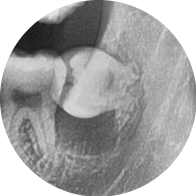

As a result of panoramic and small X-ray imaging,

an over 6 mm radiolucent lesion (dark-appearing cystic tissue) beneath the left mandibular third molar was identified,

and a tooth cyst was suspected.